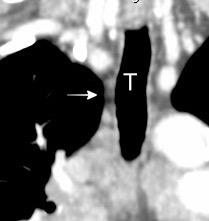

T. mixto de células

Ganglios retroperitoneales (flechas negras)

germinales del testículo izquierdo Nódulos pulmonares múltiples. (flechas verdes). Ganglios paratraqueales. (flechas amarillas). Dudoso ensanchamiento retrocrural (flechas negras)

Panda A et al. “Straddling Across Boundaries”. Thoracoabdominal Lesions: Spectrum and Pattern Approach. Curr Probl Diagn Radiol, 2015